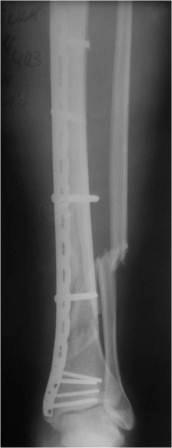

Последние рентгенограммы выглядят не очень, но и первые послеоперационные тоже не безупречны: оставался и вальгус (может лишь чуточку меньше чем сейчас) и не восстановлена длина обеих костей. Может создаться впечатление, что пластина не подвела,а просто ввиду некотрого отличия проекций деформация на вторых снимках выглядит более явной. Не совсем понятно какие винты (вроде обычные кортикальные?) применены на диафизе и зачем так близко к перелому (опять нужны первичные рентгенограммы), какую роль играет самый нижний 4.5 мм винт - он м/б в щели?

Наверное мы бы выполнили реостеосинтез:

1) ORIF малоберцовой кости, фиксация пласиной или стержнем - восстановление длины и устранение вальгуса;

2) если деформация не устранится - то новую пластину на большеберцовую, тоже MIPPO - открыто сильно лучше не будет.

Возможен и интрамедуллярный остеосинтез при наличии возможностей и умения.

Уважаемый Максим. У меня создалось впечатление, что снимки после падения фактически идентичны первоначальным, покрутите ногу под скопией чтоб проекции совпали. И... ORIF. Фиксатор тут не виновен.